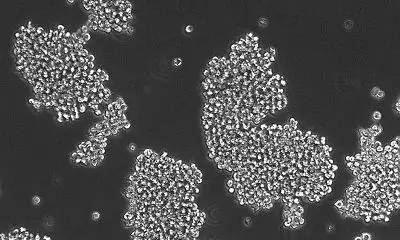

هœ¨è؟™ن¸€ç ”究ن¸ï¼Œ�,Raabeهچڑه£«ç‰ن؛؛ن»ژو‚£è€…ن½“ه†…ç–ڈو•£ه‡؛ن؛†ç™Œç»†èƒï¼Œ�,ه¹¶ن¸”让ه…¶وژ¥هڈ—èچ¯ç‰©هˆ؛و؟€�م€‚�م€‚�م€‚�م€‚�م€‚م€‚و•ˆوœوک¾ç¤؛,�,TAK228能ه¤ںé™چن½ژDIPG细èƒçڑ„ه¢و®–,�,ه¹¶ن¸”ن¼ڑé€ وˆگ6%细èƒçڑ„و®’ه‘½�م€‚�م€‚�م€‚�م€‚�م€‚م€‚